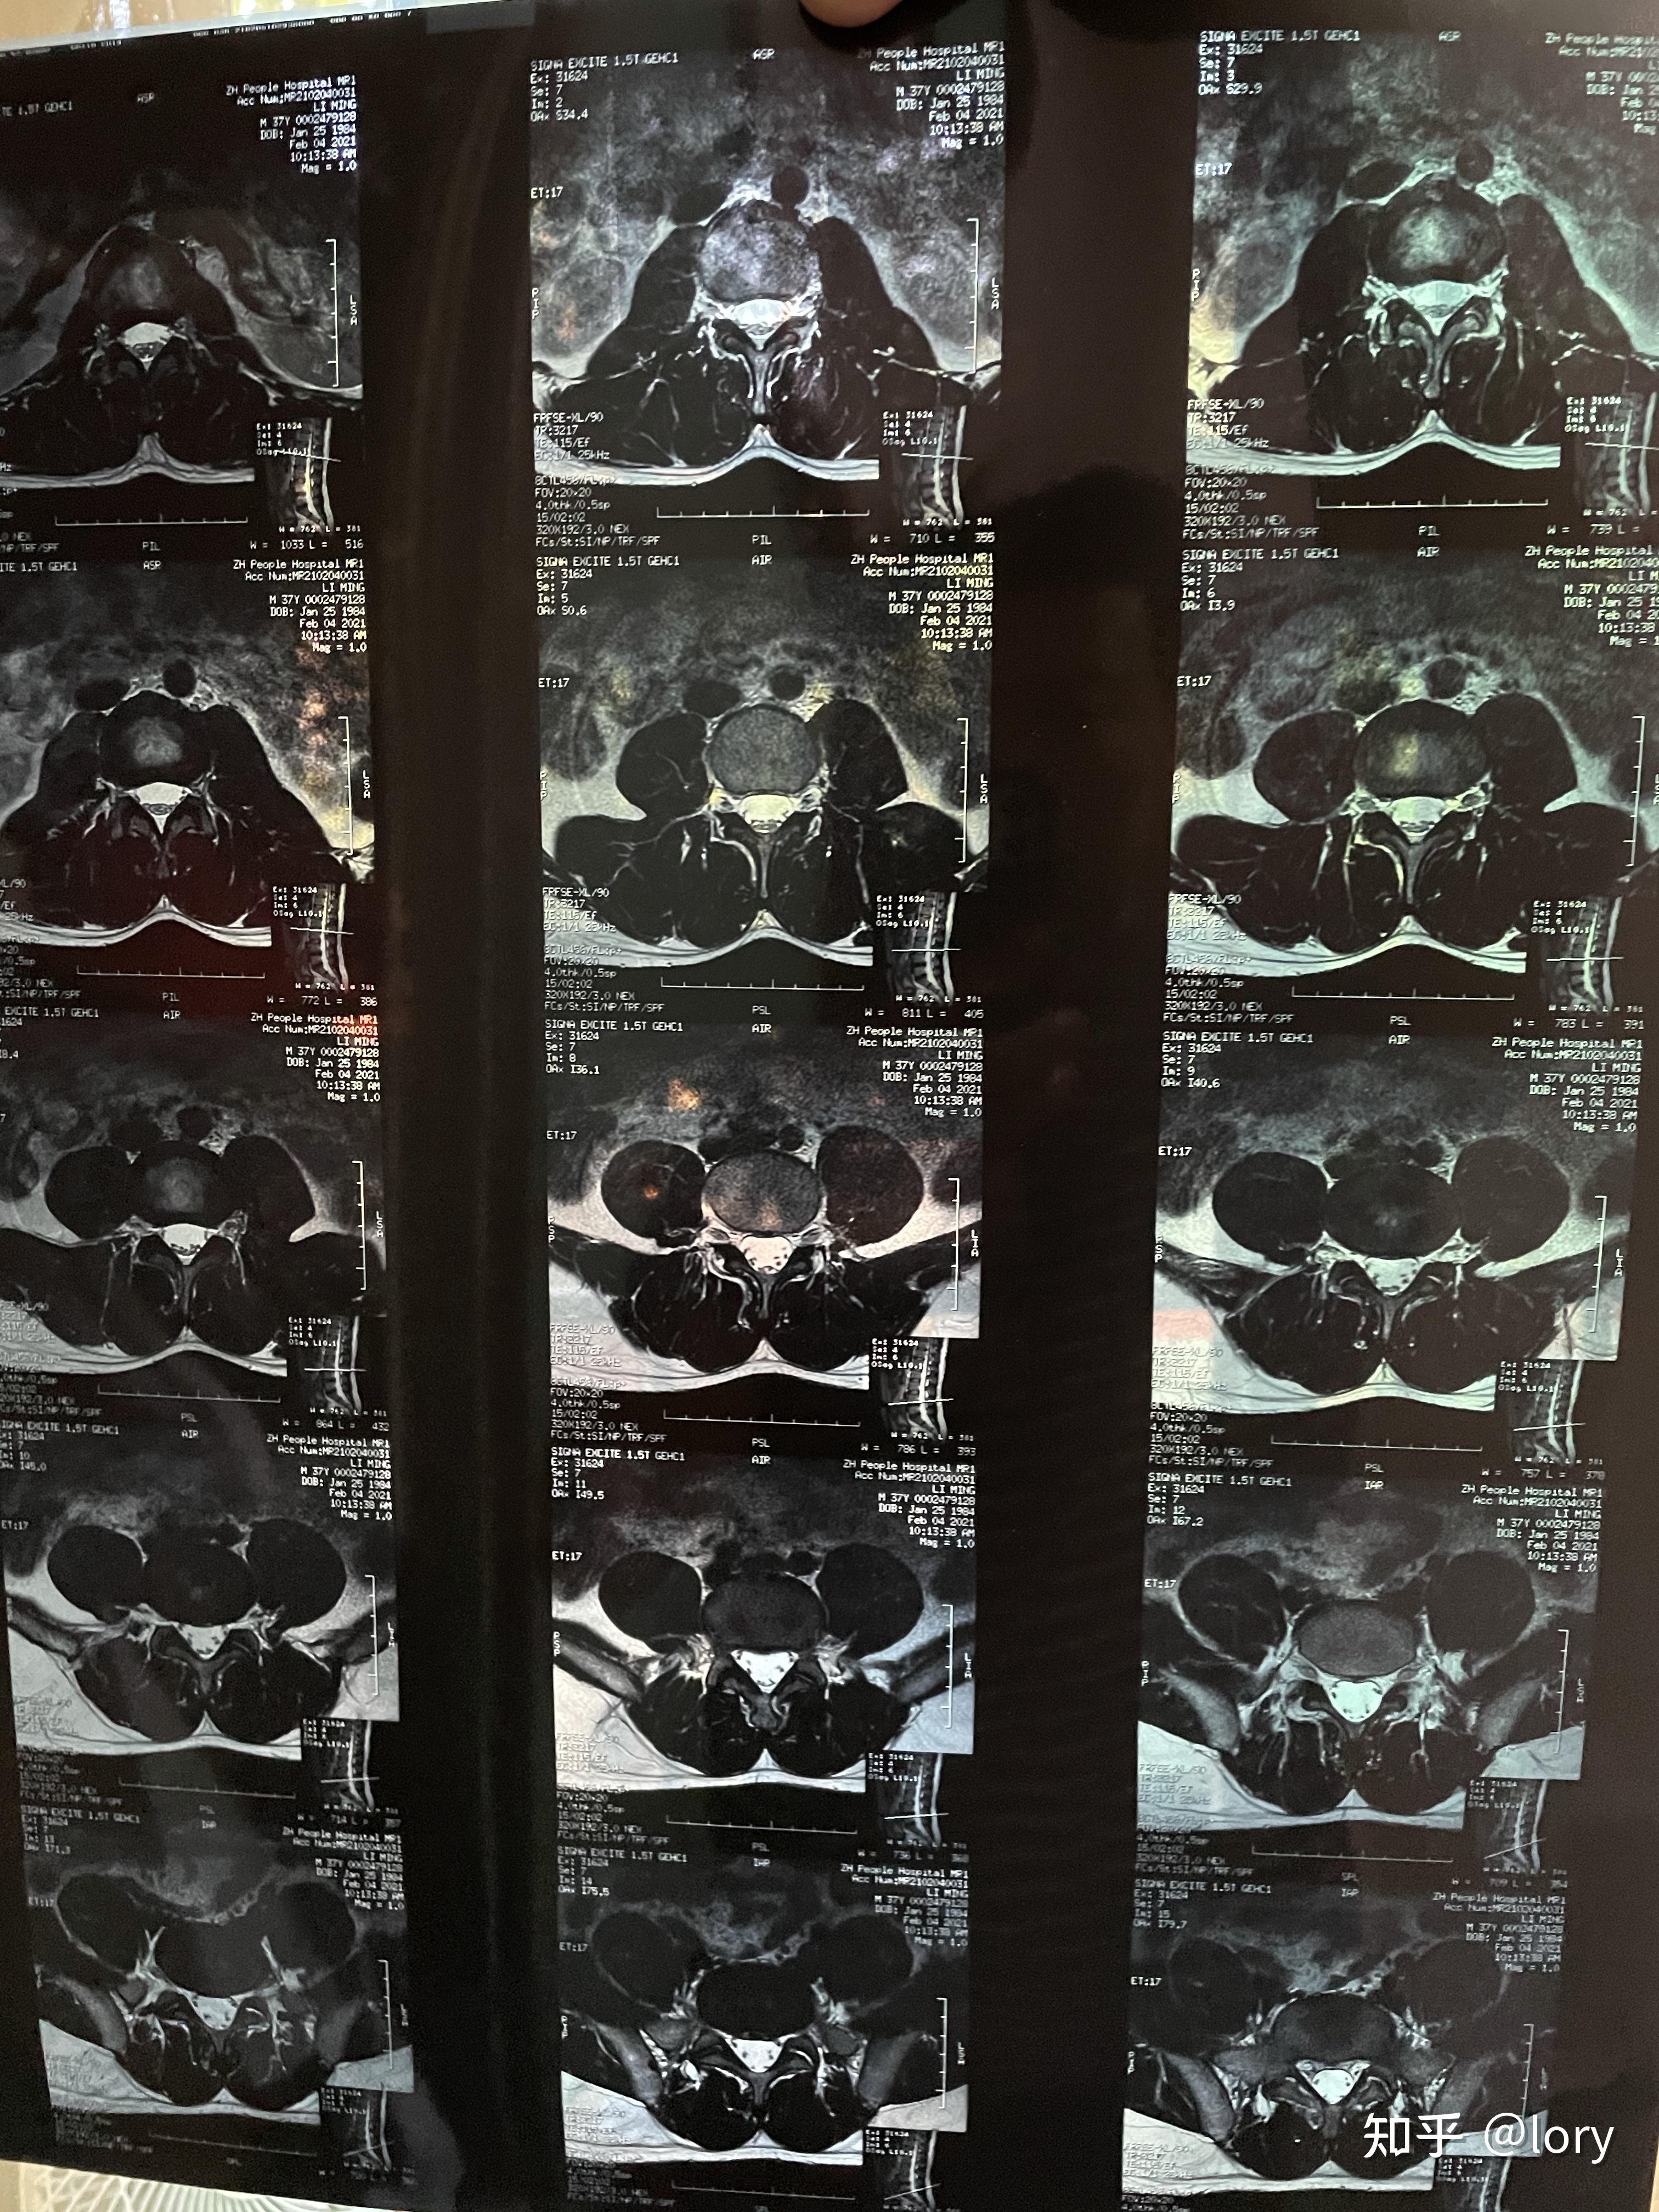

腰椎核磁共振片

膝盖及腰椎伤病核磁共振结论篮球运动

膝盖及腰椎伤病核磁共振结论篮球运动